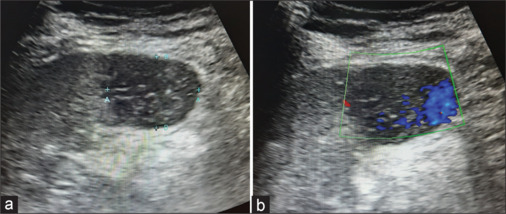

Vascular tumors constitute the most common primary tumors of the spleen. Splenic hamartoma and littoral cell angioma have been reported only in the spleen. Splenic hamartomas are rare benign vascular tumors which are incidentally detected during imaging and are seldom symptomatic. This case report describes a rare sonological appearance of splenic hamartoma in a 31-year-old female with occasional pain in the left hypochondrium.